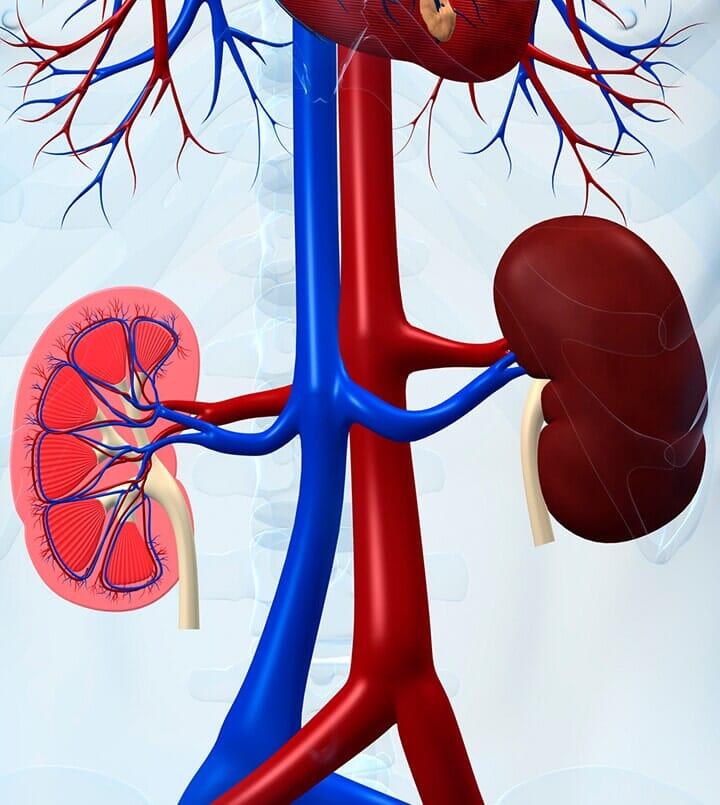

¿Sientes dolor en el riñón? Deja de sufrir de dolores intensos, el Dr. José Jorge Santibáñez Flores es un médico urólogo con consultorio en Celaya, Guanajuato, quien suma más de 10 años de experiencia en el sector de la salud.

Dile que no al bisturí con la experiencia del médico urólogo

Atención médica con ética, tecnología y precios accesibles

Dr. José Jorge Santibáñez Flores, quien cuenta con una alta especialidad en cirugía láser y laparoscopia.